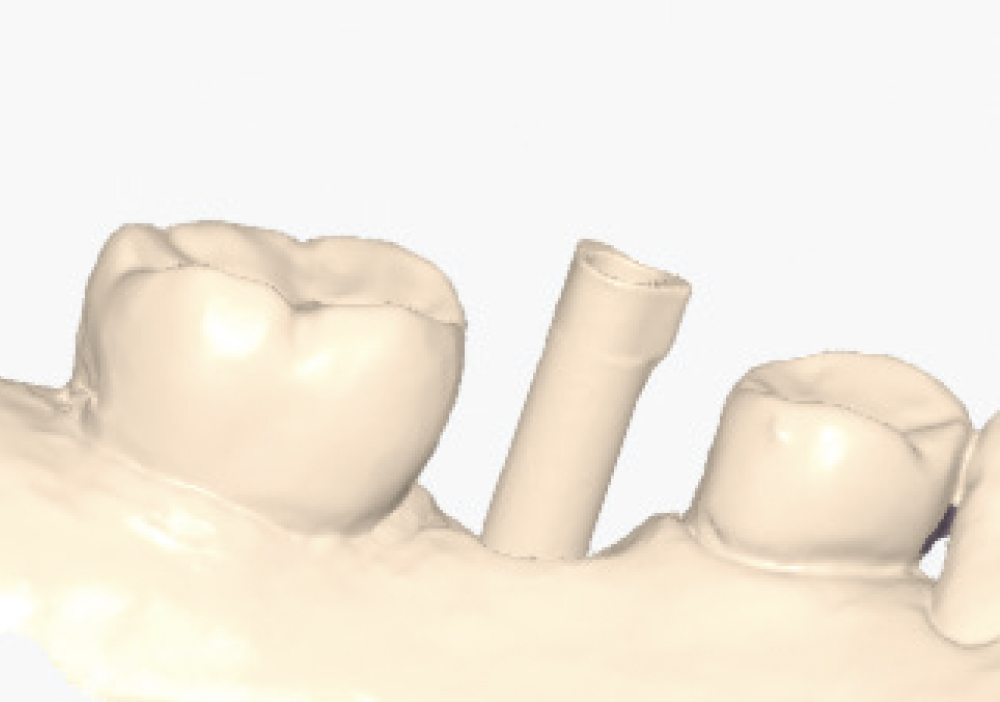

Thoroughly Scan the Scan Body Geometry

Thoroughly Scan the Scan Body Geometry. Complete, high-resolution capture of the scan body is non-negotiable. This is how laboratory software determines the precise three-dimensional position and angulation of the implant. The software matches the scanned scan body with its library file to establish the implant location in space. Scan from multiple angles to ensure all identifying features and surfaces are captured, as incomplete scan body data leads to misaligned restorations regardless of how perfect the rest of the scan appears. Verify that all reference markers, grooves, or geometric features are clearly visible in the acquired scan.

Implant post scan on left side of mouth

Implant post scan pointing down

Implant post scan close up